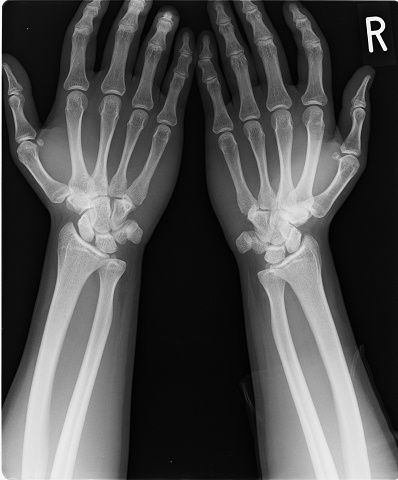

本学科の学生がオートバイで転倒し手首(手関節)を負傷して登校してきました。応急処置として固定を行い整形外科に骨折の確認をお願いしました。

レントゲン検査の結果、骨には損傷がありませんでした。TFCC損傷(軟骨損傷)と診断されました。安静にするためロングギブス固定中です。